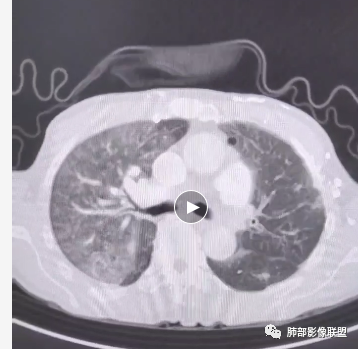

王琰:补充晨读视频

周围区域连续些看,感觉有树芽征。

Coke with ice:

如果这个树芽征明确的话,这个就不是肺水肿。可以做个最大密度投影或多方位观察再次确定是否有树芽征。弥漫性中轴间质和周围间质增厚常规就两个疾病谱,癌淋或肺水肿。而且这个人有明确的右肺明显。结合可疑树芽征,很多可以看到沿着肺动脉走形的磨玻璃影,需要可疑血源播散性转移或血管源性恶性肿瘤病变,再就是嗜血管的淋巴源性的恶性肿瘤。血管肉瘤,血管内淋巴瘤病可以这个表现,之前还碰见过一个,好像是NK/T淋巴瘤也这个表现,这个有点记不清了。